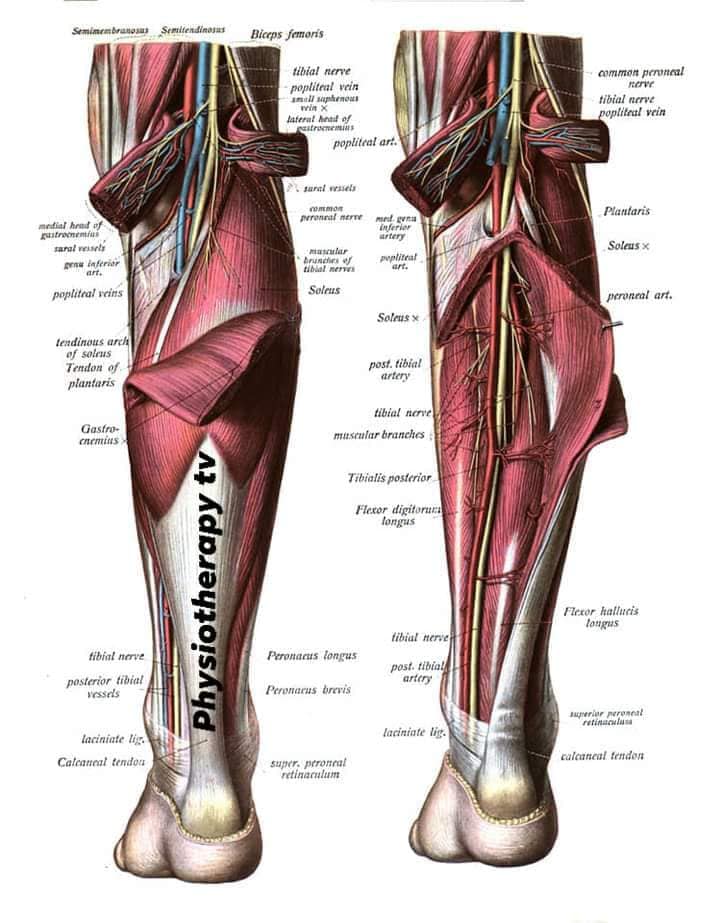

Спинні м'язи

Спинні м'язи виконують функції підтримки хребта, а також дозволяють здійснювати рухи тулуба.

Поверхневі спинні м'язи

М'язи, що піднімають лопатку: Трапецієподібний м'яз: великий м'яз, що покриває верхню частину спини. Його функція - підтримка і рух лопаток, а також забезпечення стабільності хребта.

М'язи, що ведуть лопатку до хребта: Широкий м'яз спини: великий м'яз, що розташований в нижній частині спини. Він відповідає за рухи плечей і лопаток, а також за розширення верхньої частини тулуба.

Глибинні спинні м'язи

М'язи, що забезпечують стабільність хребта: М'язи, що розташовані між хребцями: включають мускулатуру, яка забезпечує стабільність і підтримку хребта, а також дозволяє здійснювати рухи хребта.

М'язи, що здійснюють ротацію та нахили

М'язи, що забезпечують ротацію хребта: Ротаційні м'язи: допомагають у здійсненні обертальних рухів тулуба, а також у підтримці рівноваги і стабільності хребта.